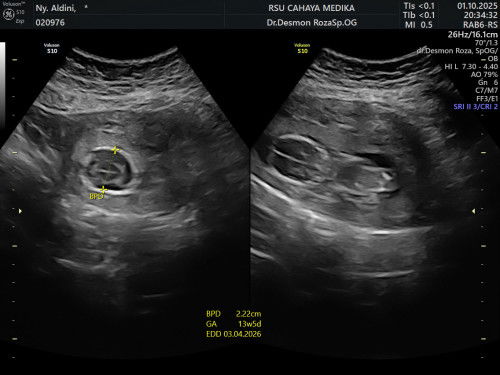

Ada ga yang punya pengalaman usia janin 12-13 week tapi ketubannya sedikit banget? Bisa ga ketubannya bertambah? Ada tips buat menambah air ketuban ga? Kemarin dokterku bilang janinnya ga oke dan kemungkinan kemungkinan buruk lainnya tapi ga dikasih solusi apapun selain nunggu 😭 tapi mana bisa kita tenang tanpa ngelakuin apapun jadi saya langsung minta rujukan dari faskes 1 buat usg fetomaternal alhamdulillah dapet tapi masih waiting list dokternya sampe tanggal 23, sambil nunggu adakah tips yang bisa bunda bunda bagi atau ada pengalaman yang sama? Boleh tolong dishare? Terimakasih bunda bunda 🙏 #bantujawab #sharing #Needadvice #askmommies